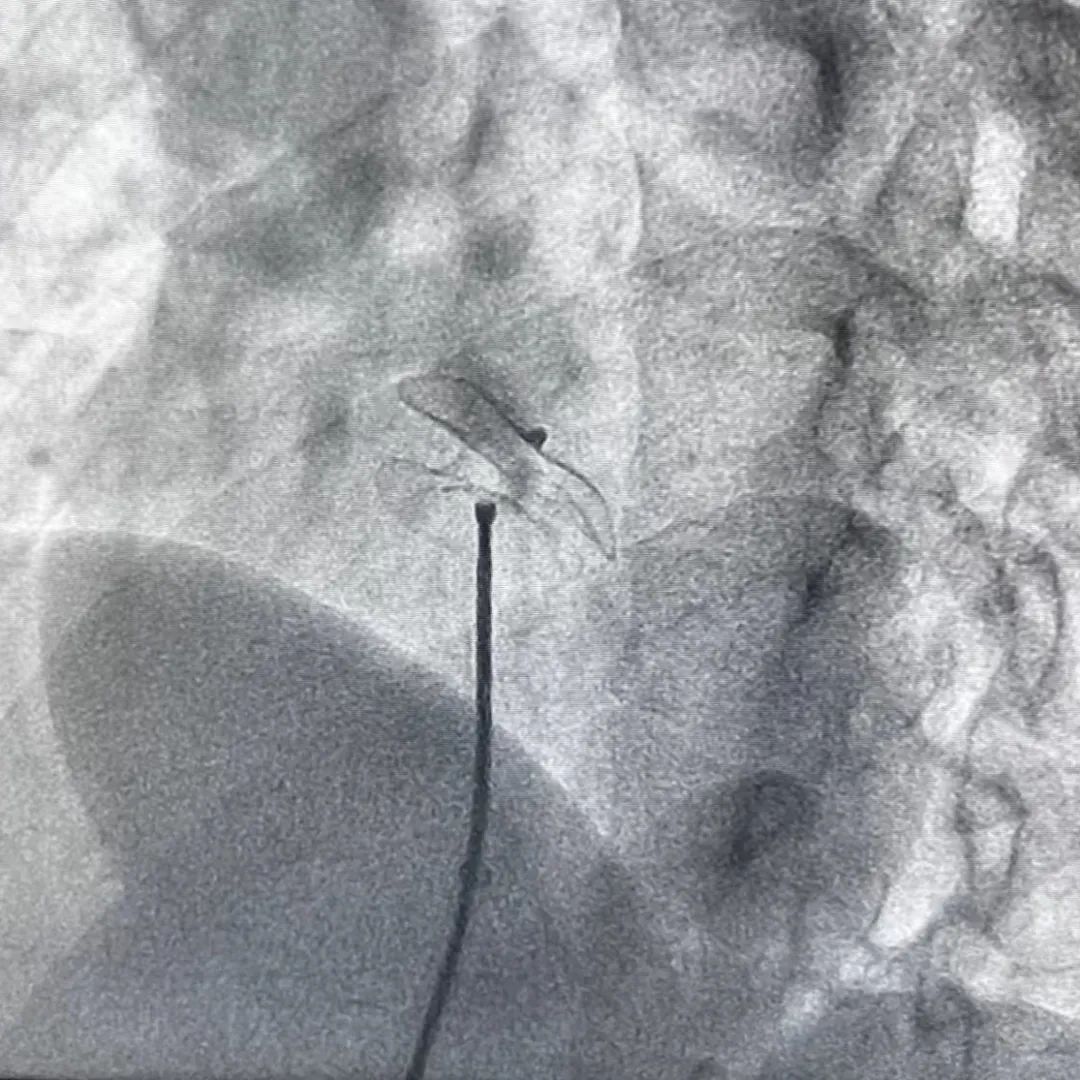

這種治療方法是業(yè)界認(rèn)可的最為安全的一種先心病介入治療方法,經(jīng)股靜脈穿刺,將封堵傘送入心房,補(bǔ)貼固定在房間隔缺損處,阻斷心房血液左向右分流,恢復(fù)正常血液循環(huán)途徑。該術(shù)式具有療效確切、創(chuàng)傷小、術(shù)后恢復(fù)快等優(yōu)勢(shì)。